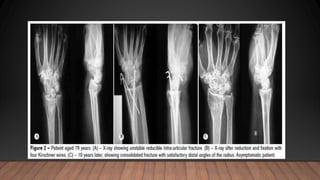

preoperative (A), postoperative (B), and latest follow-up

(C) X-ray findings for Micronail.

(C) X-ray finding